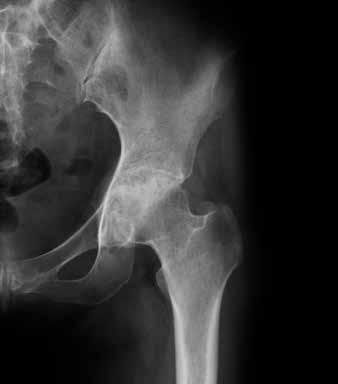

Die Diagnose einer Arthrose erfolgt mittels Anamnese (systematische Befragung zum Gesundheitszustand), körperlicher Untersuchung sowie Ausschluss anderer Erkrankungen durch eine ärztliche Fachperson. Unterstützend werden Röntgenaufnahmen gemacht, um Ausprägung und Schweregrad in den betroffenen Gelenken zu ermit-

teln. Im Gegensatz zur entzündlichen Rheumatoiden Arthritis hat die Blut untersuchung bei der Diagnosestellung der Arthrose einen untergeordneten Stellenwert. Sie kommt ins Spiel vor allem bei Mangel zuständen oder Stoff wechselstörungen.

Gesundes Hüftgelenk Arthrotisches Hüftgelenk

Wie sich die Arthrose im Laufe der Zeit entwickelt, ist von Person zu Person ganz unterschiedlich. Es können ein oder mehrere Gelenke davon betroffen sein. Ob jemand mit Schmerzen, Steifheit und Bewegungseinschränkungen rechnen muss, ist im Anfangsstadium nicht vorauszusehen. Manchmal sind auf der Röntgenaufnahme starke Veränderungen sichtbar, der Betroffene merkt jedoch kaum etwas davon im täglichen Leben. Umgekehrt sind heftige Schmerzen möglich, ohne dass im Röntgenbild ein ausgeprägter Knorpelabbau sichtbar ist.